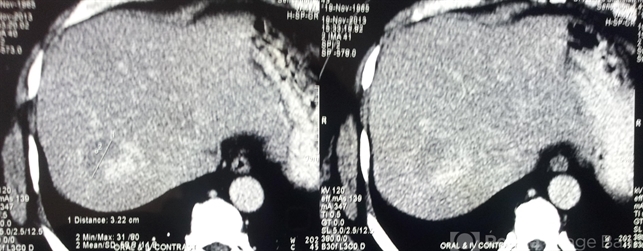

- Liver hemangioma in association with optic disc capillary hemangioblastoma in Von Hippel disease

- CT scan of chest, abdomen, and pelvis was WNL except for a small hemangioma in the liver measuring 32 mm and this hemangioma was also noticed on abdomen ultrasound as a hyper-reflective area. Brain MRI was WNL.